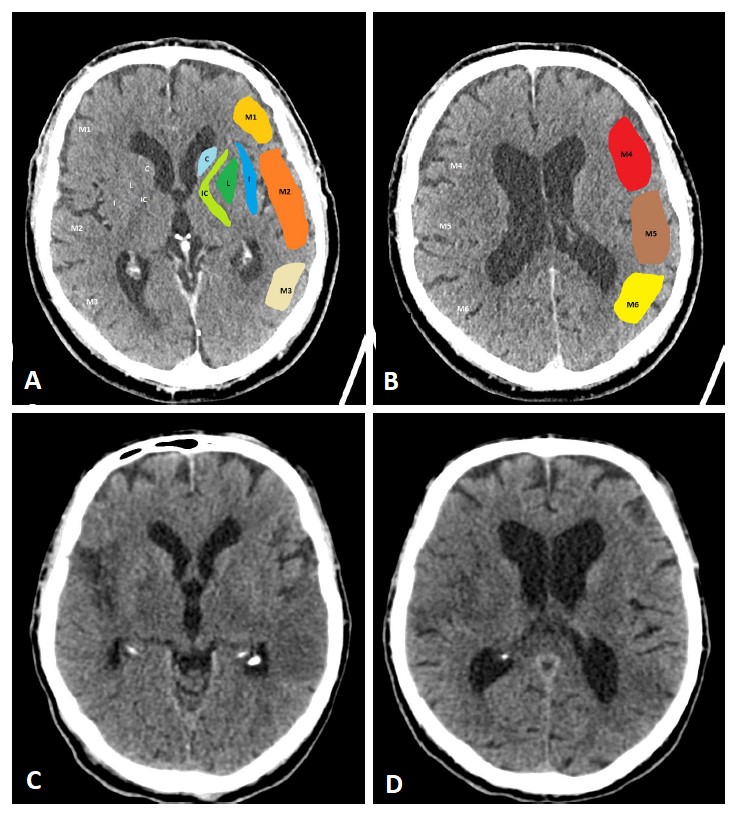

Fig. 3.pc-ASPECTS (posterior circulation ASPECTS). The pc-ASPECTS is a 10-point score evaluating the extent of ischemia in the posterior circulation. Scores of 10 points indicate no signs of ischemia in NCCT or MRI (diffusion weighted imaging, DWI). Each thalamus, occipital lobe and cerebellar hemisphere accounts for 1 point, and the mesencephalon and pons account for 2 points. Fig. 3 shows fluid attenuated inversion recovery (FLAIR) sequences because of better image quality.